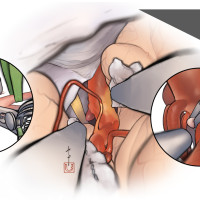

監修:谷川 緑野 / 札幌禎心会病院脳卒中センター

FEN2022シリーズ

術後イラストシリーズ